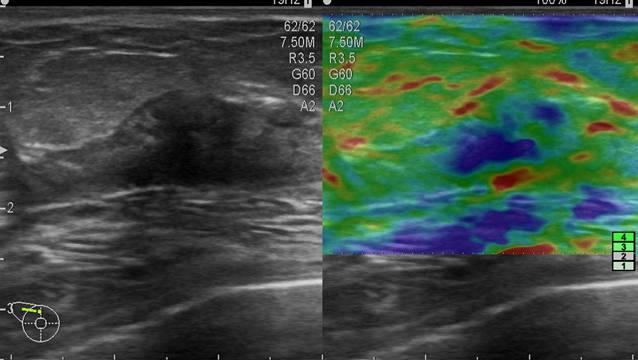

Ung thư vú

» Thông tin: Nữ giới – 76 tuổi.

» Lâm sàng: Khối tuyến vú.